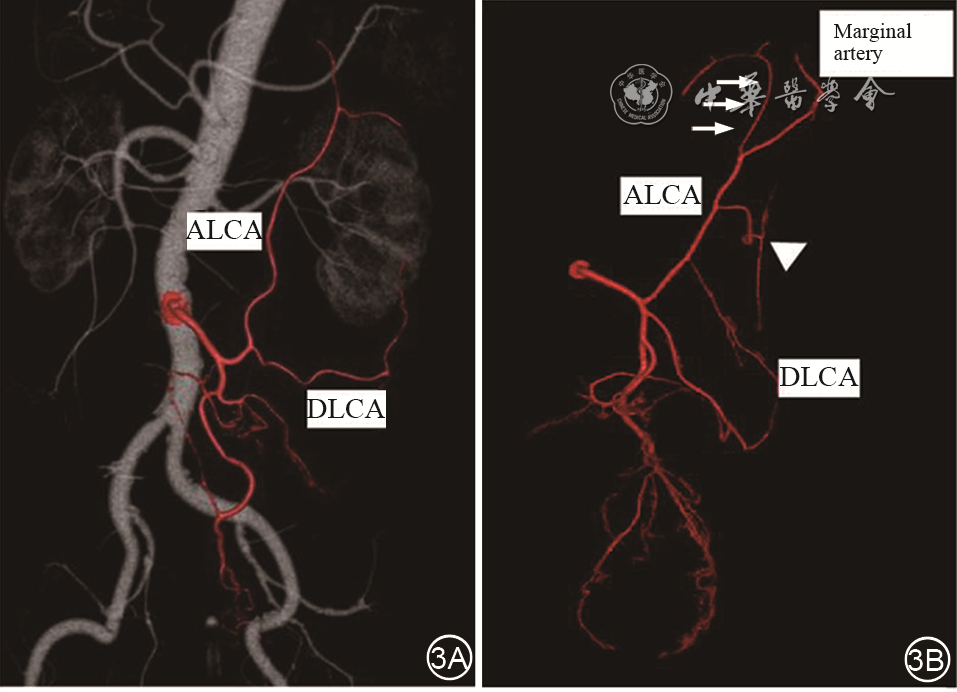

IMA分支有许多不同的分型,LCA既可单独起源于IMA,也可与乙状结肠动脉(sigmoid artery,SA)及直肠上动脉(superior rectal artery,SRA)共干,或与SA共干。Ⅰ型,直、乙共干型,LCA单独发出,约占38%;Ⅱ型,左、乙、直全共干型,约占45%;Ⅲ型,左、乙共干型,约占12%;Ⅳ型,无左型,约占5%。绝大多数LCA走向结肠脾曲(图2图3[6],但有约5%的LCA直接汇入远端降结肠边缘弓,5%的患者LCA可缺如;LCA也可走行与乙状结肠靠近,再沿降结肠上行至结肠脾曲[3]。副左结肠动脉(ALCA)出现与IMA变异、直径和走行有关。156例尸解发现:14.5%存在ALCA的同时,12%的LCA缺如、变细,走行更靠近SA[10]

图3 左结肠动脉的血管成像(引自参考文献6)。3A:左结肠动脉通常与肠系膜下静脉伴行,供应结肠脾曲。3B:左结肠动脉的多个分支,ALCA:左结肠动脉升支;DLCA:左结肠动脉降支